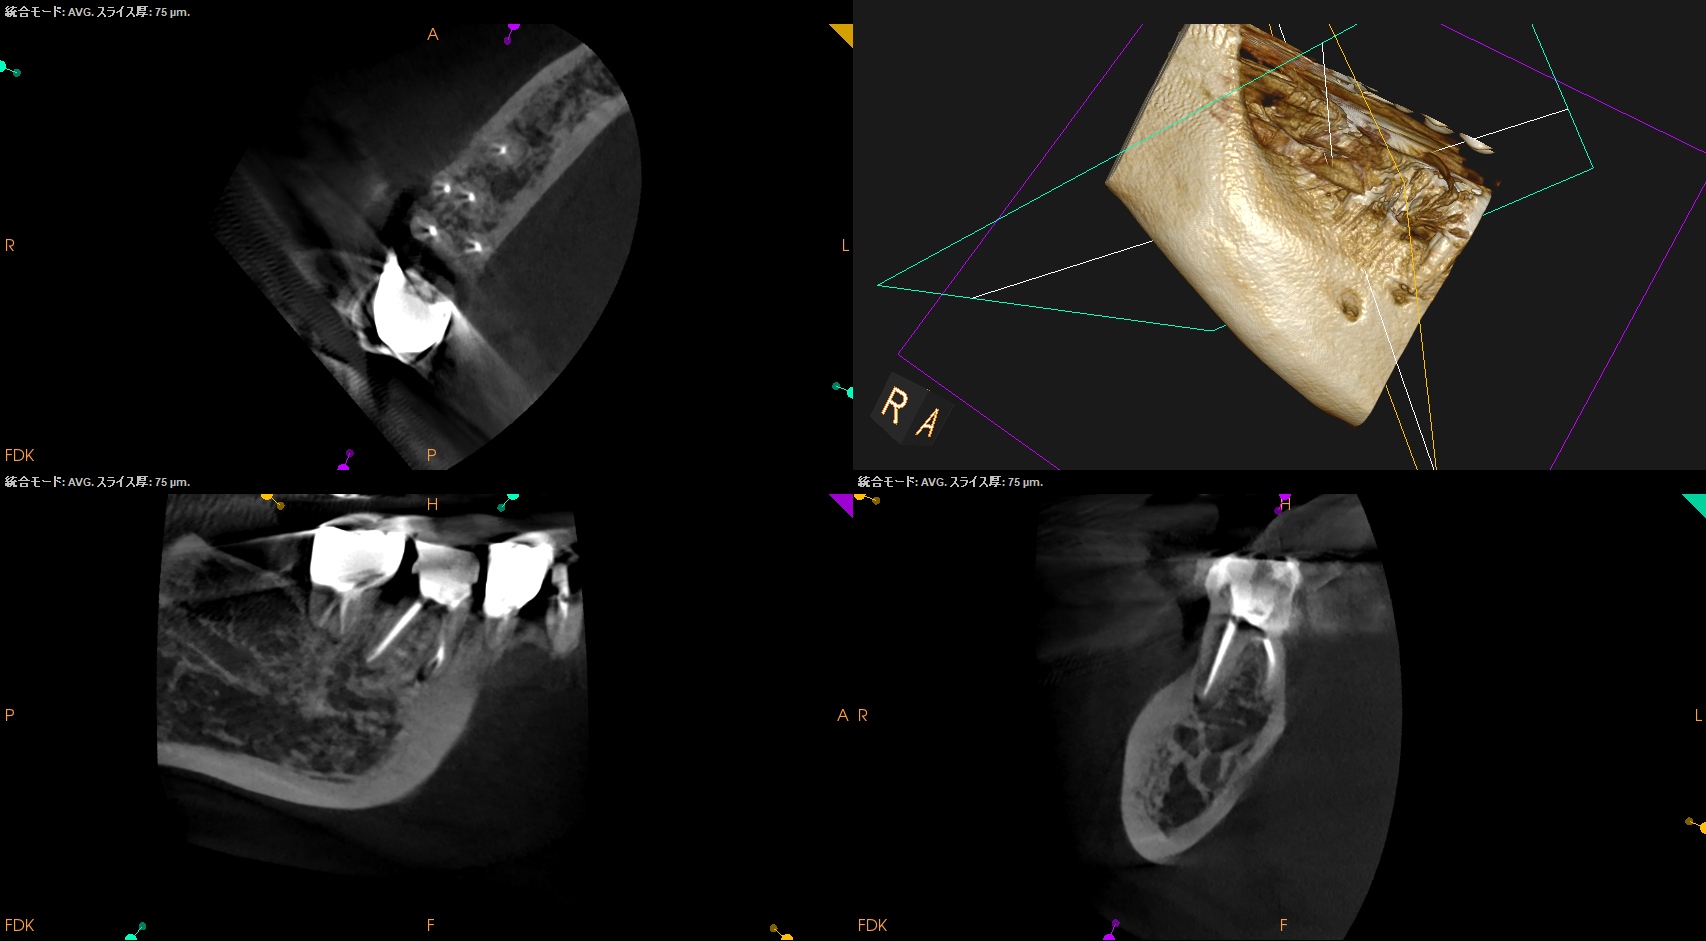

ちなみに形成中に私が見ている絵はファイルが根管に入り形成されている様(動き)ではない。

私が見ているのはこの絵の矢印部分である。

#10.05

#20.05

#25.V

#40.04

形成前に根管にファイルを入れてラバーストッパーからReference Pointまでの距離が形成できる根管の距離であるということがわかる。

この距離は、形成の都度、短くなり形成量は減少していく。

これを無理に押し込めるとレッジができる。

Freedmanが言う通りだ。